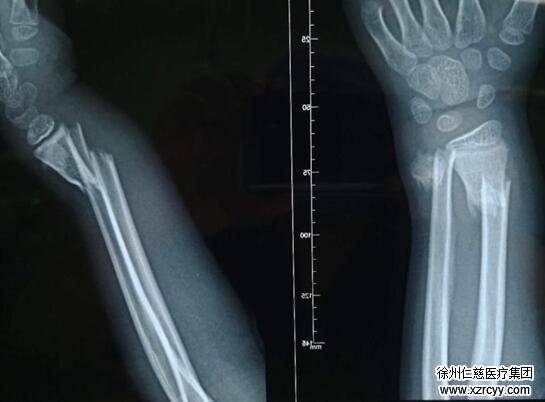

都说“伤筋动骨一百天”,一开始,冬冬爸妈也没有太心急。可眼看半个多月过去了,孩子还成天喊疼,他们坐不住了,又带着孩子跑到医院复查,然而结果却让人颇为遗憾,X光片显示,冬冬右腕的骨折部位又错位了。情急之下,冬冬爸妈带着孩子来到了徐州的三甲医院就诊,这时简单的手法复位已经远远不能解决问题了,必须进行手术。冬冬的手腕伤在这里得到了确诊:右尺桡骨远端骨折。于是,骨折后一个月,冬冬在全麻状态下接受了右尺桡骨骨折切开复位钢针内固定术,术后予以消炎治疗。

本以为这次可以治愈了,可术后一个多月,桡骨骨折部位还是没有愈合,并且冬冬的右手腕出现了明显的畸形,严重制约了他的手部大动作。这让冬冬爸妈大惑不解,这看似不起眼的一个跟头,竟然一波三折,让孩子连连遭罪,孩子的手还有救吗?

看到家长焦急的表情,齐伟亚主任认真看过冬冬的X光片后,发现孩子的骨折部位发生了明显的错位,桡骨骨折部位不愈合,孩子的右手已经出现了严重的畸形。